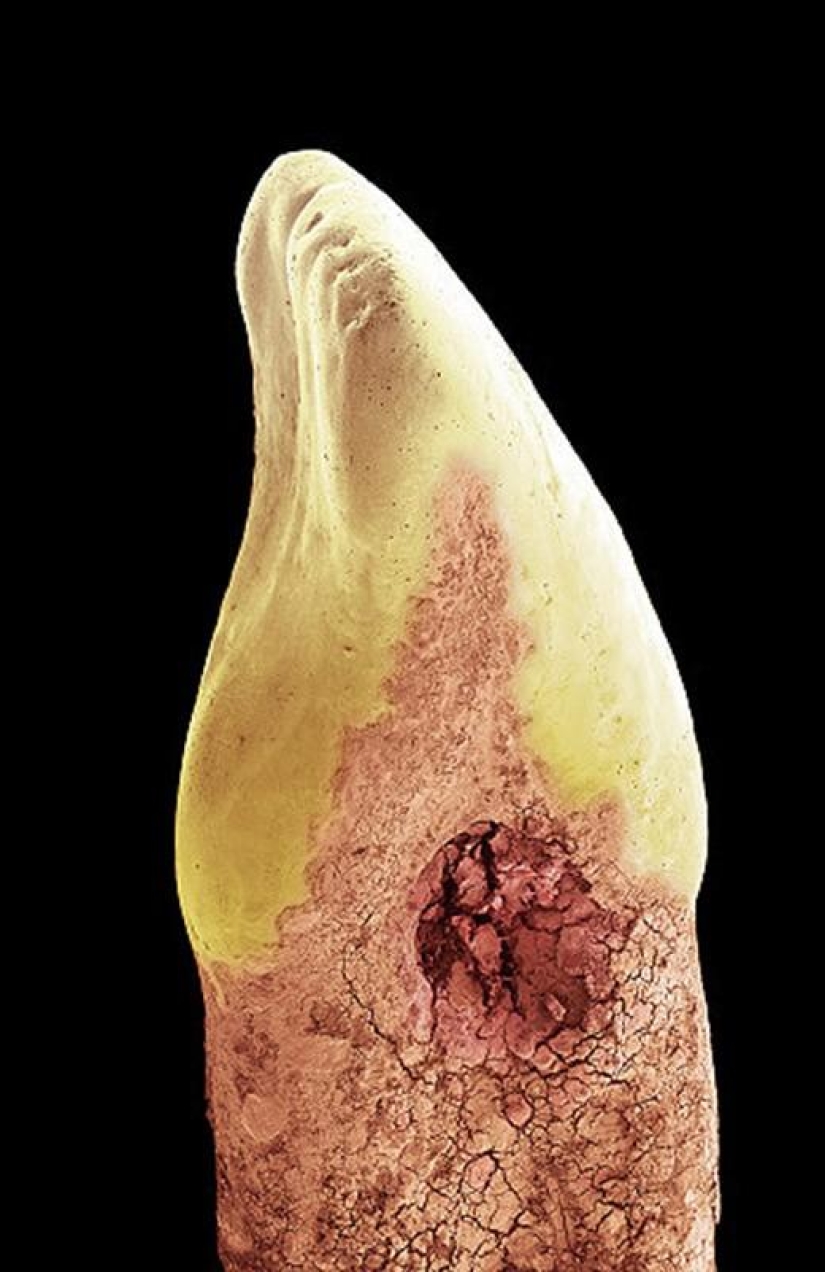

Diente de leche. La mayoría de los dientes humanos están hechos de dentina, una sustancia que recubre la cavidad que contiene tejido conectivo blando, vasos sanguíneos y nervios. Luego, la corona del diente queda cubierta por esmalte (blanco en la foto de arriba), una sustancia más fuerte y mineralizada que protege la dentina de los ácidos de la boca. En la raíz de un diente, la dentina está protegida por una sustancia llamada cemento (rosa), que sirve como medio por el cual los ligamentos periodontales pueden adherirse al diente para lograr estabilidad. (SPL/Barcroft Media)

Corona de un diente de leche. Su raíz se ha separado mediante un proceso conocido como reabsorción dental temporal. Esto fue causado por la presión del diente permanente en crecimiento. (SPL/Barcroft Media)